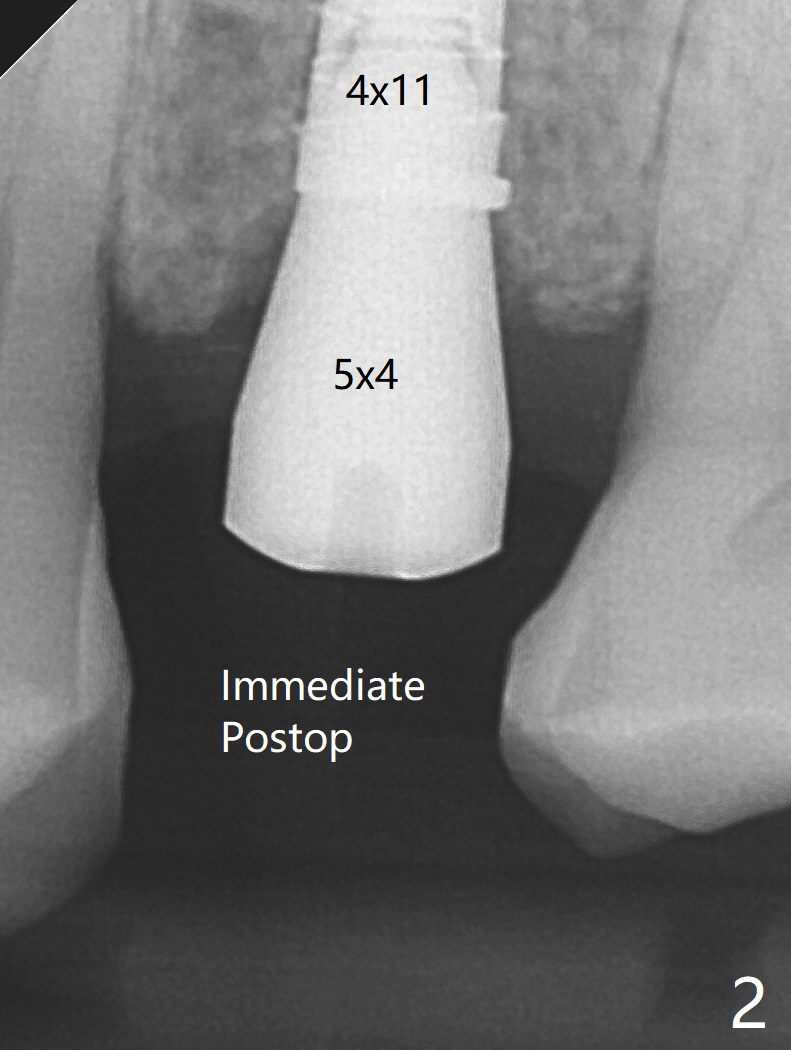

To avoid contact between the future abutments and the mesiobucco-distal crest, a 5.5 mm profile drill is used.  It appears that a 5x4 mm healing abutment has clearance from the crest (Fig.2 ).  A pair abutment is completely seated 6 months postop (due to coronavirus, Fig.8).